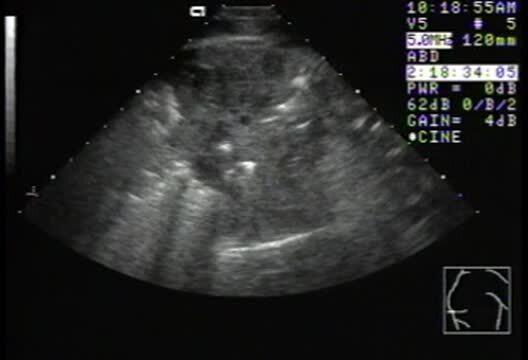

Rhodococcal pneumonia, foal

Thoracic ultrasonographic examination of a 3-month-old foal with rhodococcal pneumonia. Note pulmonary consolidation with air-filled lung visible in the periphery of the image. Small, fluid-filled abscesses can be identified in the pulmonary parenchyma.

Courtesy of Dr. Bonnie R. Rush.